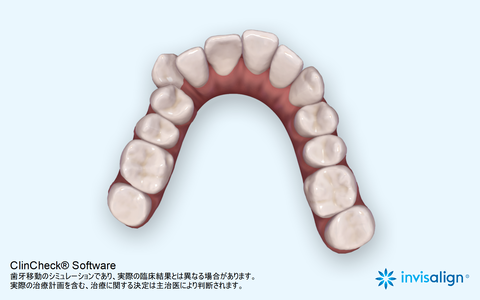

上の歯。引っ込んだ歯が歯並びの中に納まっている。

下の歯。こちらも歯並びの中に納まっている。